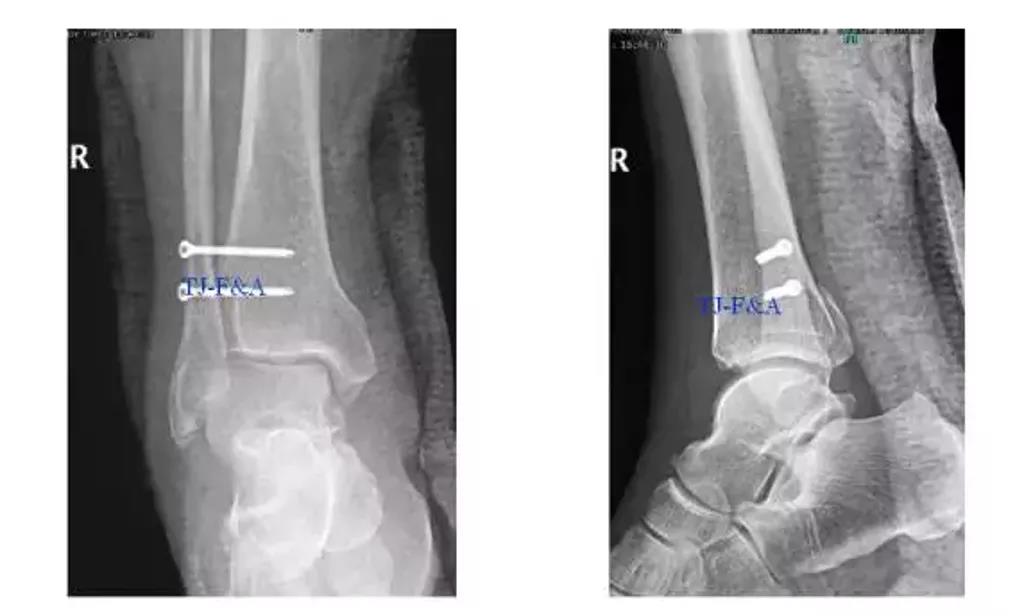

术后DR

术前DR

术中: